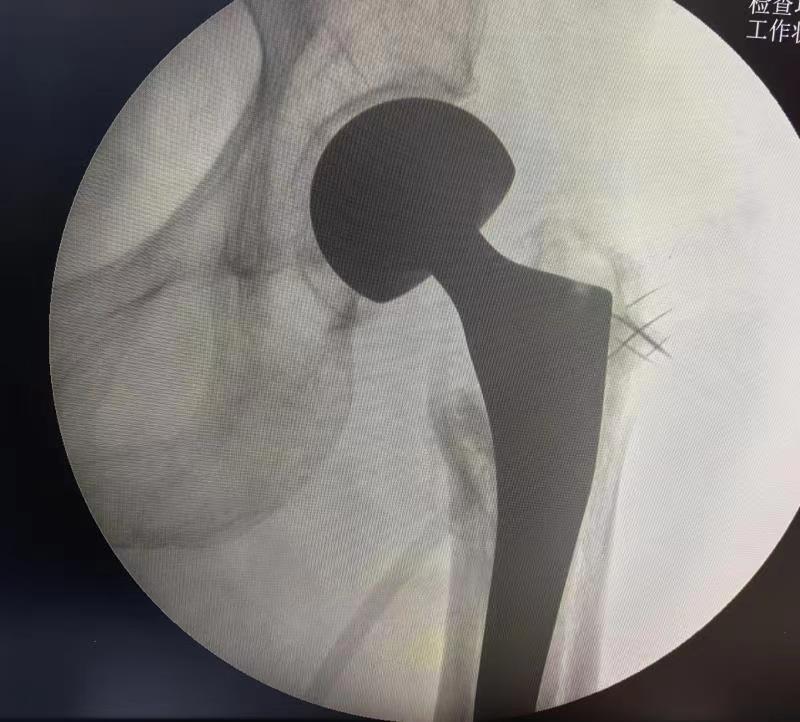

今日,我院一位90岁高龄髋关节置换患者康复出院。蚌埠市康复医院(市四院)李叶刚副院长带领骨科医护人员,一早来到病房看望患者。患者,女,90岁高龄,因摔伤导致“左股骨粗隆间骨折”入院,医院骨科团队给予髋关节置换手术治疗。术后3天,患者在康复师的指导帮助下开始床边站立锻炼。术后第7天,主管医生详细交代出院康复锻炼方法,及其他注意事项后,患者出院回家休养。

高龄患者粗隆间骨折以粉碎性居多,大小粗隆及外侧壁粉碎破裂,且伴有不同程度的骨质疏松。保守治疗需长期卧床,易发生下肢深静脉血栓、压疮、坠积性肺炎、泌尿系统感染等并发症,加之老年人基础疾病较多,长期卧床保守治疗的病死率可高达34%,被称为“人生最后一次骨折”。因此针对粗隆间骨折,在身体条件允许的情况下,尽可能早期手术治疗,传统内固定手术可以满足床上早期康复锻炼,但不能早期下床活动。采用髋关节置换治疗该类患者,可以满足患者早日下床活动及早期康复需要。